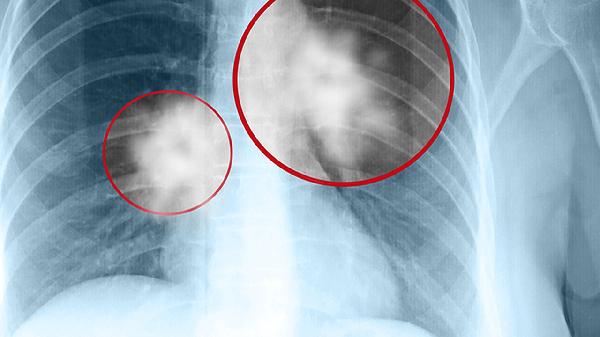

軀干和四肢是癌癢最常出現(xiàn)的區(qū)域,瘙癢感可能呈現(xiàn)持續(xù)性或陣發(fā)性,皮膚表面通常無明顯皮疹,但可能因搔抓出現(xiàn)抓痕或繼發(fā)感染。部分患者會(huì)感到瘙癢從某一固定點(diǎn)開始,逐漸擴(kuò)散至更大范圍。惡性腫瘤如淋巴瘤、白血病乳腺癌等更易引發(fā)此類癥狀,可能與腫瘤細(xì)胞釋放的組胺、蛋白酶等物質(zhì)刺激神經(jīng)末梢有關(guān)。

少數(shù)情況下癌癢可能集中在特定部位,如肛周瘙癢可能與直腸癌相關(guān),外陰瘙癢需警惕婦科腫瘤。這類局限性瘙癢常伴隨局部皮膚顏色改變或異常分泌物?;羝娼鹆馨土龌颊呖赡艹霈F(xiàn)飲酒后皮膚瘙癢加重的特殊表現(xiàn),這種癥狀具有較高提示價(jià)值。